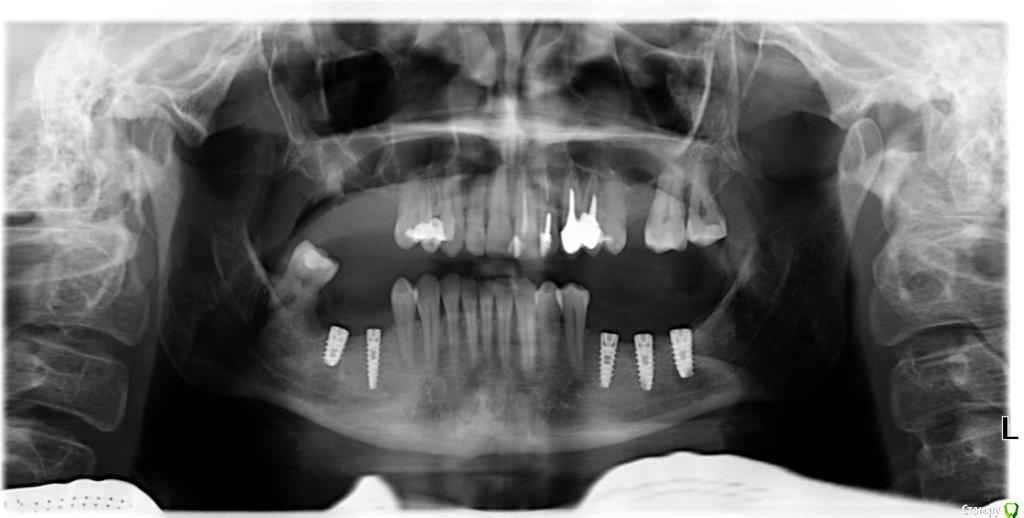

Oksana-p Опубликовано 23 мая, 2016 Поделиться Опубликовано 23 мая, 2016 (изменено) Ув. специалисты. Помогите пжл разобраться в моей ситуации. В январе были установлены импланты, справа одномоментно с удалением. Костную пластику даже не предлагали. Сказали, что кости в достачном объеме. Хирург уже во время имплантации слева убедил, что желательно поставить третий имплант. По его словам - на место 7 зуба (так и записал в карточке - 35, 36 и 37). Когда прошли отеки десны, во время снятия швов, я задала вопрос- зачем мне поставили имплант в район 8 зуба. На что мне был дан ответ, что все поставили правильно. Неделю назад поставили формирователи, И теперь стало очевидно, что крайний имплант стоит ровно напротив моего верхнего 8-го зуба. Помогите пжл разобраться, это развод или в моей ситуации это действительно нормально. Я знаю, что восьмые зубы не имплантируются вообще, да и свои в основном идут на удаление. Не будет ли у меня проблем в дальнейшем? И еще вопрос на место жевательных зубов слева (35 и 36) хирург поставил очень тонкие формирователи (около 2 мм в диаметре). Справа на место 45 зуба формирователь поставил так, что он вообще не в десне, а под десной. И я вижу верх импланта, где постоянно собирается налет. Я понимаю, это ненормально. Сразу говорил, что будет делать пластику десны при установке ФДМ. Теперь уже говорит, что посмотрит, может будет нужна пластика при установке коронок. Все импланты изначально чувствовала по контуру в десне и они просвечивались через десну. Я несколько раз обращалась к хирургу, но каждый раз мне отвечали, что все хорошо. Но все пять стоят выше уровня кости (это у него такой метод установки имплантов). Не поздно ли сейчас делать пластику десны? И возможна ли она сейчас вообще. У меня вообще уже состояние на грани нервного срыва. А мне еще верх нужно имплантировать. Не могу сделать срезы Кт, только ссылка получается. И панорамный снимок сразу после имплантации. Снимки после установки формирователей не делал хирург. https://yadi.sk/d/rjtafJuUrqYK4 Изменено 23 мая, 2016 пользователем Oksana-p Ссылка на комментарий

Oksana-p Опубликовано 25 мая, 2016 Автор Поделиться Опубликовано 25 мая, 2016 (изменено) Возвращаюсь к теме. На прием через неделю, тогда буду просить и панорамный снимок сделать. Сегодня один хирург, изучив мои снимки и КТ, объяснил, что нужно было кость подсыпать сразу, и очень тонкая десна.Сейчас уже смысла подсыпать кость нет-ничего к импланту не прирастет. Максимум, что можно сделать в моем случае -пересадить с неба десну. (процедура я так понимаю не из приятных). Да и вообще по моим имплантам прогноз очень сомнительный. А мой хирург до сих пор утверждает, что у меня все хорошо. Сижу и плачу- ни денег , ни зубов. Уже думаю, может коронки не ставить, а зашить все и съёмник поставить.... Боюсь, чтобы не получилось как у этого пациента. У меня тоже уже виден верх импланта справа...... Да и клиника не самая дешевая. И врача хвалили. Руководство так вообще говорит- "скажите спасибо, хоть так поставили". http://forum.stom.ru/topic/25147-chto-delat-s-implantom-mis/page-2 Изменено 25 мая, 2016 пользователем Oksana-p Ссылка на комментарий